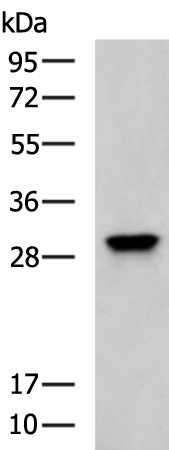

分类: 科研抗体货号: P10606别名:应用: WB,IHC反应种属: Human